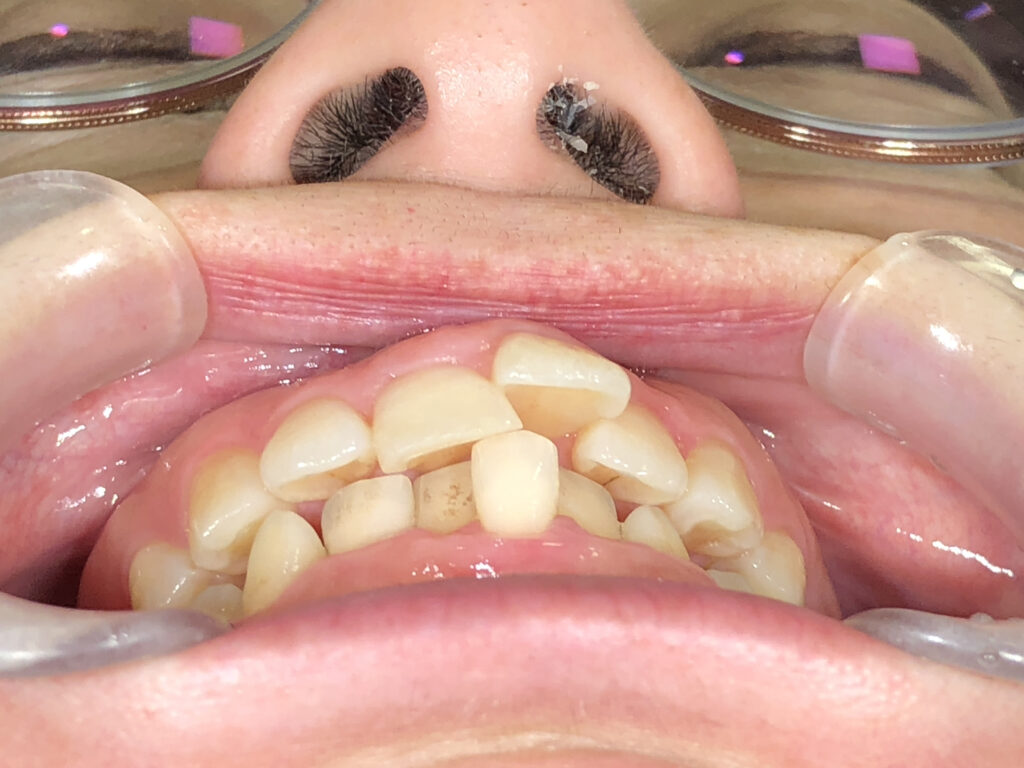

前歯部あおり

治療前